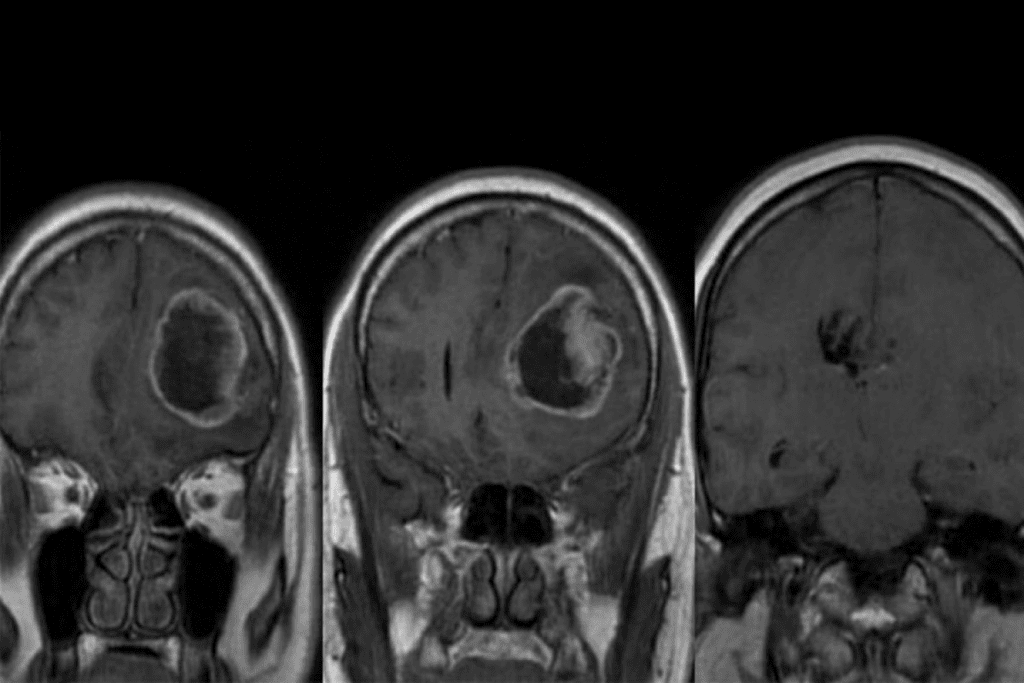

- Masses or Tumors: MRI scans can spot tumors in the brain, spine, and organs.

Brain MRI Results: What They Mean

Brain MRI scans can show many things, from nothing to serious problems. It’s important to understand what they mean for your health.

Common Brain MRI Findings and Their Significance

Scans can find issues like white matter changes and cerebral atrophy. They might also spot cysts or aneurysms. Some findings are okay, but others need more attention.

White matter changes are common in older people. They might be due to aging or health issues. Cerebral atrophy, or brain shrinkage, is also normal but can sometimes mean a health problem.

Potentially Serious Brain Abnormalities

Some MRI results show serious issues that need quick action. These include signs of stroke, tumors, or multiple sclerosis. Doctors and radiologists must carefully look at these to decide what to do next.

For example, if an MRI shows a stroke, acting fast can help a lot. Finding a tumor might mean talking about treatments like surgery or chemotherapy.

Follow-up Recommendations for Brain MRI Findings

What happens next after a brain MRI depends on the results. For minor findings, doctors might suggest waiting and watching with more scans. If a serious condition is found, a treatment plan will be made with specialists.

It’s key for patients to talk to their doctors about MRI results. This way, they can understand what the findings mean and what to do next. This teamwork helps ensure patients get the best care for their situation.